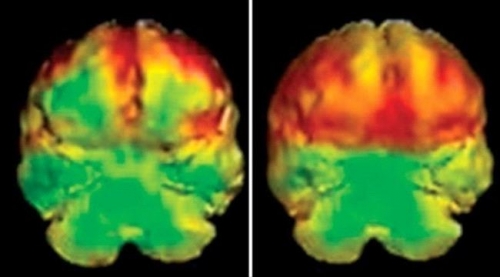

نقص الانتباه وفرط النشاط والحركة مشكلة عصبية تتطوّر خلال الطفولة، ويمكن أن تستمر بعد البلوغ. وقد لاحظ العلماء وجود مثيرات تحرّك وتفاقم أعراض المشكلة مثل عدم ضبط النفس والانفعالات، ونقص التركيز. إليك ما يفاقم أعراض نقص الانتباه: